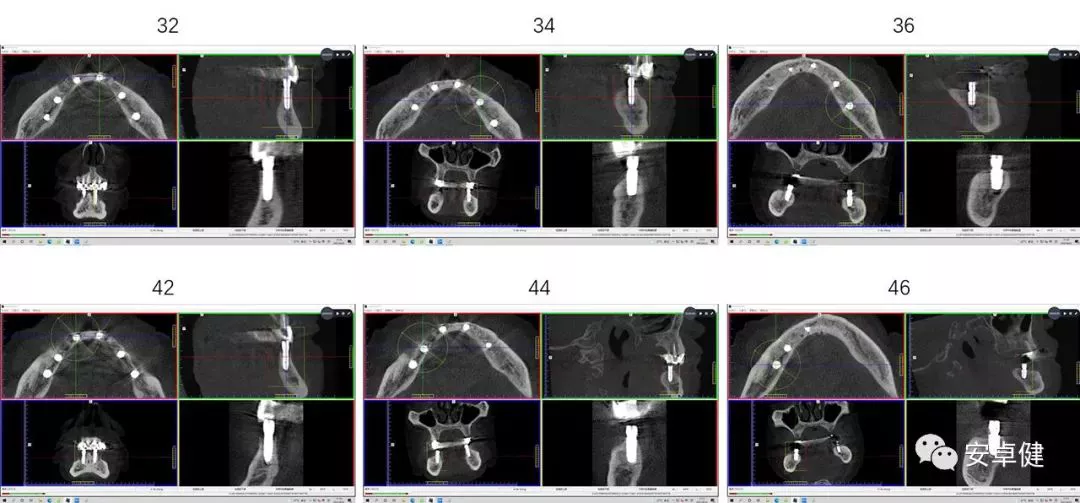

▷ 植体材料

• Anthogyr Axiom® BL REG Φ3.4mm×12mm (32位点植入);

• Anthogyr Axiom® BL REG 3.4mm×10mm (42位点植入);

• Anthogyr Axiom® BL REG 4.6mm×8mm (36位点植入、46位点植入);

• Anthogyr Axiom® BL REG 4.0mm×10mm (34位点植入、44位点植入);

术后即刻CBCT示种植体三维植入位置良好,唇舌侧骨板可

二期复诊CBCT影像学检查示种植体周围骨密度良好,骨量可

种植两年后复诊CBCT影像学检查示种植体周围骨密度良好